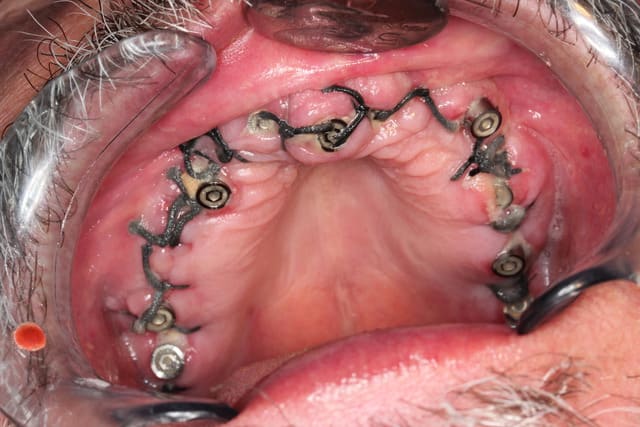

Et voilà ce ne fut pas facile mais c est fait

Tjs plus content de l avoir fait que de la voir à faire LOL

Euh oui je sais le détartrage du bas n a pas été fait mais vu l urgence le travail en haut primait largement

Choukroun Joseph

01/10/2013 à 10h20

PP, beau travail comme d'habitude.

il faudrait quand même que tu penses à passer à un monofilament pour tes sutures.. ces gros boudins, c'est un peu dépassé..